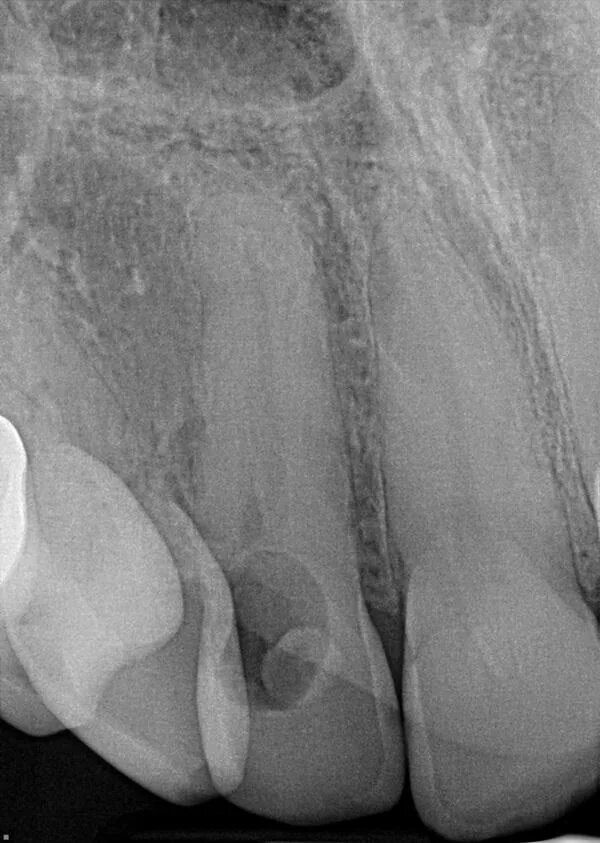

Резорбция ткани